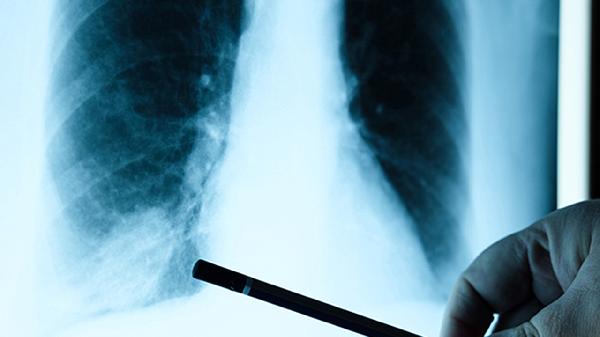

肺结节不可怕!研究做好5件事,防止癌变风险剧降

听说体检报告上出现"肺结节"三个字,很多人的第一反应就是手抖。先别急着脑补电视剧情节,这年头查出肺结节的人能凑齐十个微信群,真正需要担心的比例比中彩票还低。就像青春痘可能留疤但不代表毁容,肺结节的存在未必和癌症划等号,关键要看我们怎么科学应对。

一、肺结节≠肺癌判决书

1.体检仪器的火眼金睛

现在CT机分辨率比老式设备提升了N个level,连3毫米的"小芝麻"都能捕捉到。二十年前可能根本发现不了的微小阴影,如今统统现形,这才造成肺结节检出率飙升的假象。